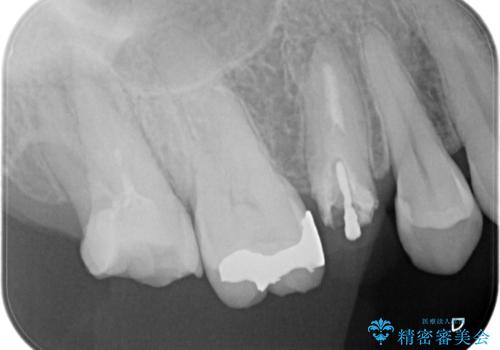

- 左上7番の奥歯に、根尖部の大きな病変を認め来院されました。レントゲンと精密検査の結果、歯の根の先に膿が溜まっている状態と診断。歯を残すことを第一に考え、精密根管治療による改善を目指す治療計画を立案しました。治療においては、細菌の侵入を徹底的に防ぎ、病変部を確実に除去するために、ラバーダムと歯科用顕微鏡を併用することを提案しました。